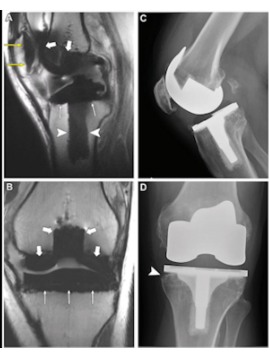

Figure 1. MRI Results of knee replacement surgery

Knee replacement surgery, also known as knee arthroplasty, is a surgical procedure to replace the damaged parts of the knee joint with artificial implants (prostheses) made of metal and medical-grade plastic that function like a natural knee. This procedure aims to relieve pain, restore mobility, and improve your ability to walk comfortably again.

- High-Resolution Knee MRI (3 Tesla MRI), RS Abdi Waluyo is equipped with an advanced 3 Tesla MRI, which provides extremely detailed imaging of the knee joint and soft tissues. This allows doctors to accurately assess the extent of joint damage and plan the surgery with precision.